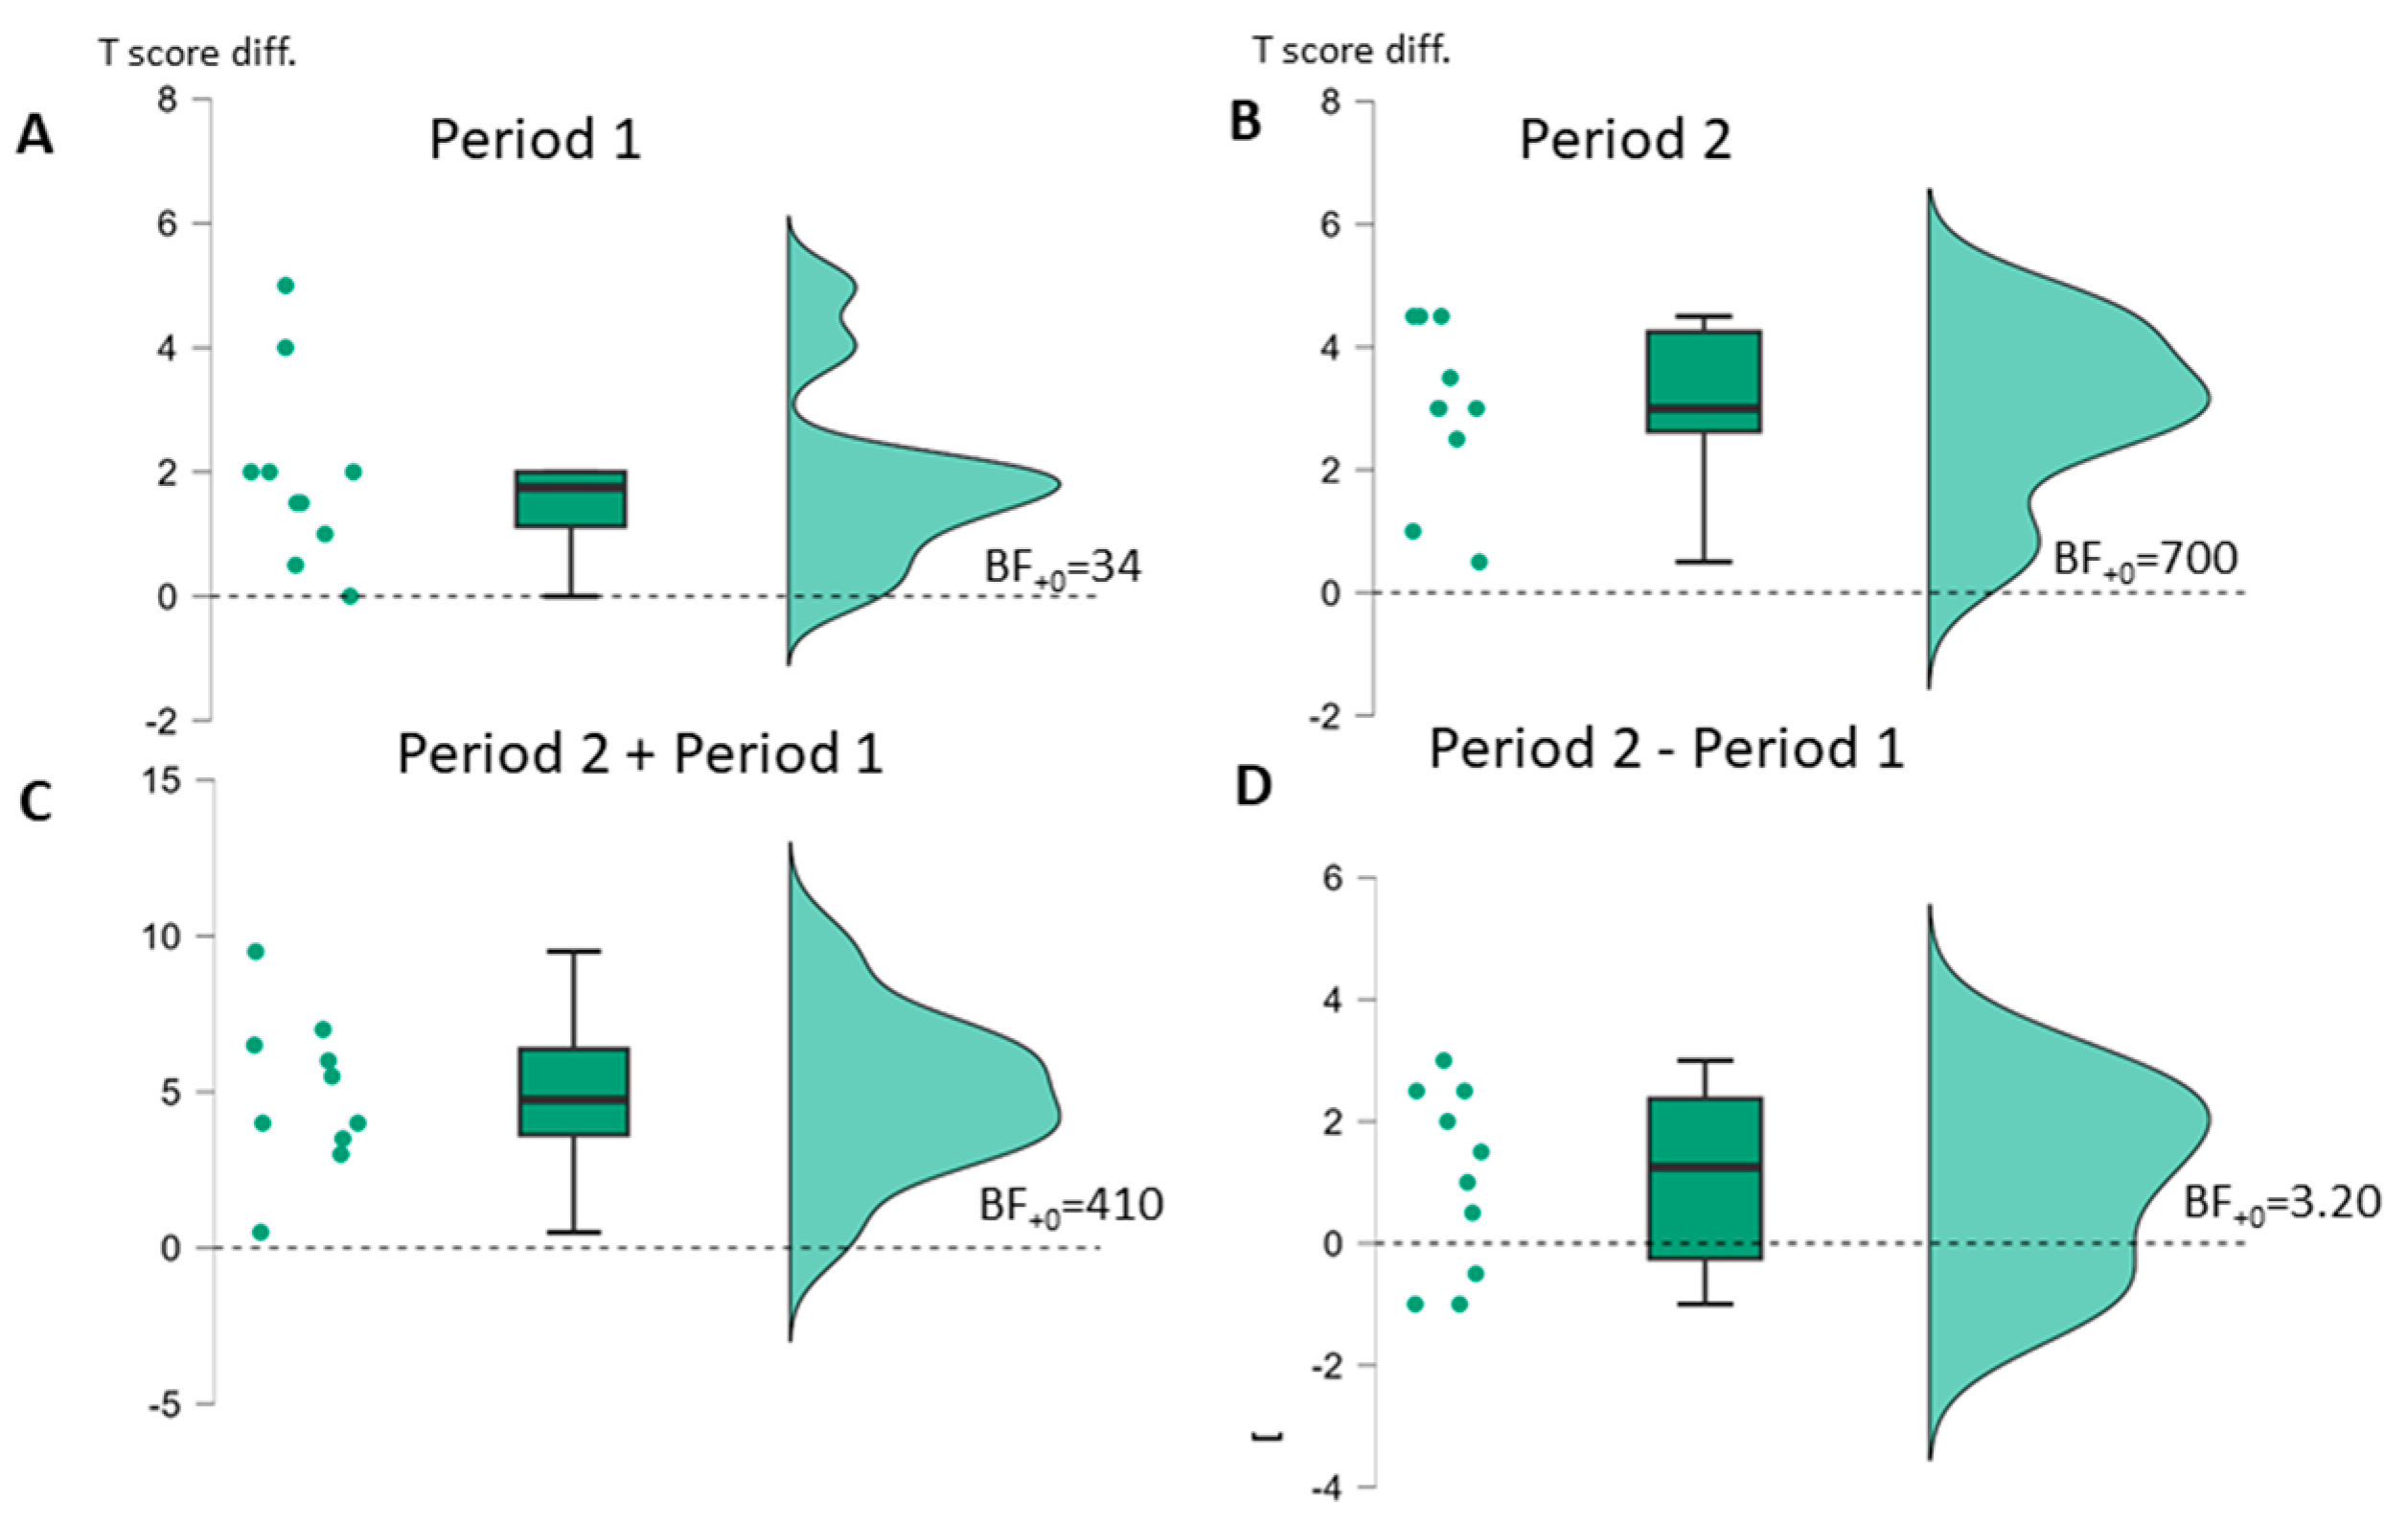

| B | Period 1 | Period 2 | Period 2−1 | Period 1 + 2 | ||||||||

| BIAS (n = 10) | t(9) * (p-v.) | Cohen d [95%-CI] | Bayes Factor | t(9) * (p-v.) | Cohen d [95%-CI] | Bayes Factor | t(9) * (p-v.) | Cohen d [95%-CI] | Bayes Factor | t(9) * (p-v.) | Cohen d [95%-CI] | Bayes Factor |

| Profile | 4.06 (0.001) | 1.29 [0.55–∞] | BF+0 34 | 6.80 (<0.001) | 2.15 [1.15–∞] | BF+0 700 | 2.22 (0.027) | 0.70 [0.10–∞] | BF+0 3.20 | 6.26 (<0.001) | 1.98 [1.03–∞] | BF+0 410 |

| ASV | 1.69 (0.063) | 0.54 [−0.04–∞] | BF+0 1.65 | 3.68 (0.003) | 1.16 [0.46–∞] | BF+0 21 | 0.31 (0.38) | 0.10 [−0.43–∞] | BF0+ 2.56 | 3.52 (0.003) | 1.11 [0.42–∞] | BF+0 17 |

| AUT | 3.26 (0.005) | 10.03 [0.36–∞] | BF+0 12 | 5.46 (<0.001) | 1.73 [0.50–∞] | BF+0 176 | 1.37 (0.102) | 0.43 [−0.12–∞] | BF+0 1.14 | 6.21 (<0.001) | 1.96 [1.02–∞] | BF+0 390 |

| ELIZ | 0.23 (0.41) | 0.07 [−0.45–∞] | BF0+ 2.71 | 2.49 (0.017) | 0.79 [0.11–∞] | BF+0 4.59 | 1.71 (0.060) | 0.54 [−0.0–∞] | BF+0 1.70 | 2.04 (0.036) | 0.65 [0.05–∞] | BF+0 2.56 |

| NACH (n = 9) | 4.14 (0.002) | 10.38 [0.57–∞] | BF+0 31 | 3.09 (0.007) | 1.03 [0.32–∞] | BF+0 9.19 | 1.94 (0.044) | 0.65 [0.02–∞ | BF+0 2.91 | 4.34 (0.001) | 1.45 [0.62–∞] | BF+0 39 |

| LSV | 2.84 (0.010) | 0.90 [0.26–∞] | BF+0 7.23 | 2.75 (0.011) | 0.87 [0.23–∞] | BF+0 6.40 | 0.14 (0.45) | 0.04 [−0.48–∞] | BF0+ 3.36 | 4.63 (<0.001) | 1.46 [0.67–∞] | BF+0 68 |

| LLES | 3.36 (0.004) | 10.06 [0.38–∞] | BF+0 14 | 1.61 (0.072) | 0.51 [−0.06–∞] | BF+0 1.49 | −0.05 (0.52) | −0.02 [−0.54–∞] | BF0+ 2.56 | 2.78 (0.011) | 0.88 [0.24–∞] | BF+0 6.65 |

| SCHR | 1.38 (0.100) | 0.44 [−0.12–∞] | BF+0 1.15 | 2.81 (0.010) | 0.89 [0.25–∞] | BF+0 6.92 | 0.35 (0.37) | 0.11 [−0.42–∞] | BF0+ 2.47 | 3.30 (0.005) | 1.04 [0.37–∞] | BF+0 13 |